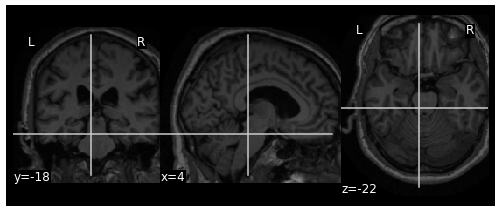

but when executing the same code (and the same inputs) with nilearn v0.6.1, the output image is not cropped at the right values:

It seems that there was some refactoring work on the file nilearn/image/resampling.py at the commit ee1f25a908d8357b4fba84dab1d2b7018e9f5e04 . It's maybe related to the changes on the behavior of this function?